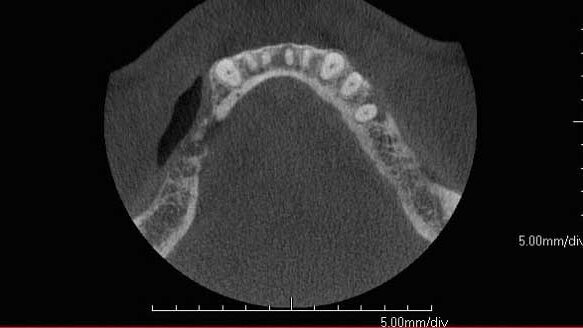

The PreXion CBCT scanner and treatment-planning software allow the clinician to properly diagnose and treatment plan edentulous patients based on the final restoration design. A preliminary diagnostic CBCT scan (Fig. 1) is beneficial to properly visualize in three dimensions the extent of bone loss and the prognosis of existing dentition.

Based on a dual-scan protocol (Figs. 2a, 2b), the final tooth position and prosthetic outcome is transferred onto a digital treatment-planning protocol. The treatment-planning software allows the clinician to propose the proper implant position based on anatomical limitations.

This data can be utilized to fabricate a surgical guide for guided implant placement, resulting in minimally invasive surgery, increased accuracy and faster healing and restorative times. A postoperative CBCT scan confirms the accuracy and final implant position (Fig. 3).